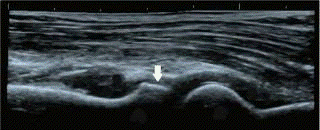

УЗИ суставов в настоящее время все активнее внедряется в клиническую практику. Благодаря короткому времени выполнения и безвредности УЗИ его можно проводить не только в специализированных кабинетах. Достоинством метода является также существенный объем получаемой диагностической информации. При УЗИ можно изучать состояние костей, мягких тканей, связок и хрящей (рис. 3-8), визуализировать даже незначительные количества жидкости.

Рис. 8. УЗИ локтевого сустава (норма). Стрелкой указана головка лучевой кости